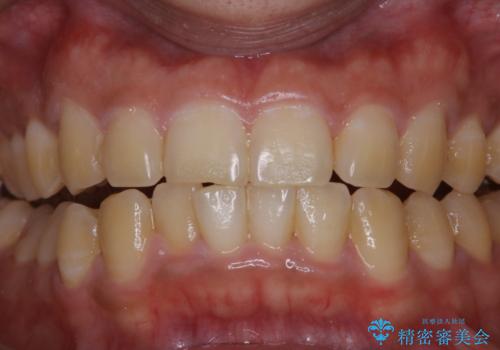

数年ぶりに歯のクリーニング(PMTC)